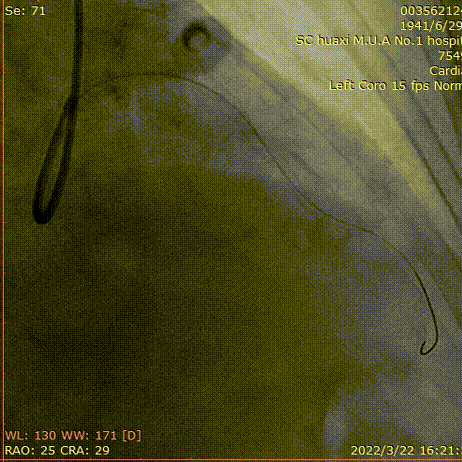

说明:高压球囊扩张后,支架仍无法通过,2.5预扩球囊锚定,送入Telescope™导引延长导管到前降支中远段。

说明:沿Telescope™导引延长导管输送支架。

说明:评估前降支开口及左主干病变,球囊拘禁对角支,植入左主干到前降支支架。

说明:最后造影结果。